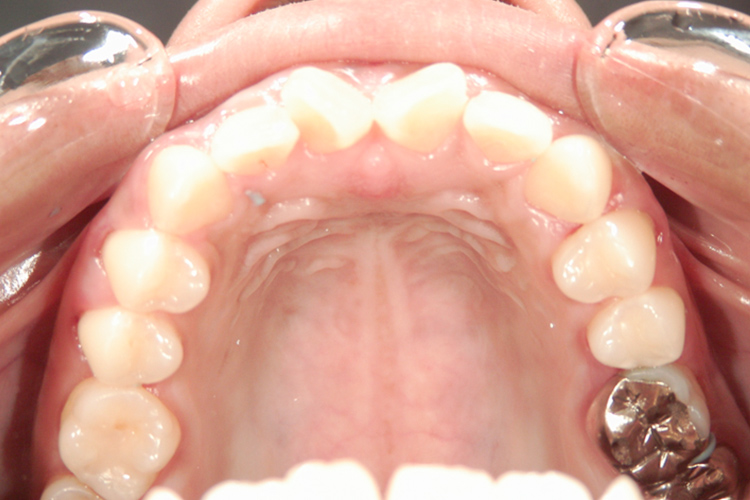

矯正前

矯正後